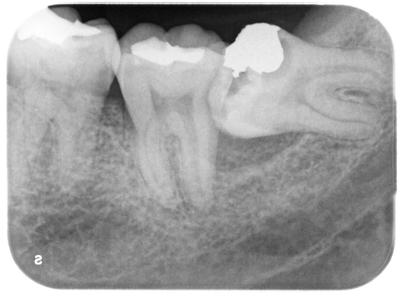

他院からの左下7、神経治療依頼。

左下8(親知らず)をブラッシング不良のまま長期間放置してきたため虫歯になり、さらに手前の7部に虫歯が波及し、神経治療を余儀なくされたケース。

根管充填後の写真。

根管治療は問題なく終了したが、当院での検査では周囲の骨が大きくダメージを受けており予後不良が予測される。